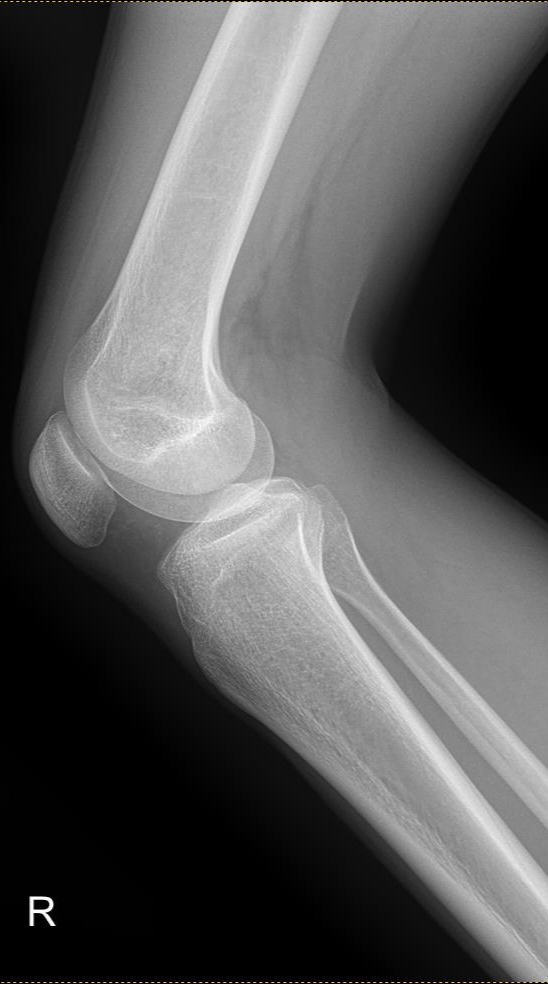

эксперты военно врачебной комиссии помогайте Аноним 16/10/25 Чтв 15:57:12 1645083 Ответ

в общем болит спина в районе поясницы при стоянии или ходьбе (где-то через 20-30 минут +-), началось в середине июля этого года после поднятия тяжести в саду. К врачам не обращался. Потом сходил в военкомат и получил б3. Понял что с такой проблемой мне в армии будет тяжко и погнал по неврологам. В общем вот пикрил мрт. Чё думаете? дадут хотя бы отсрочку на полгода на полечить?